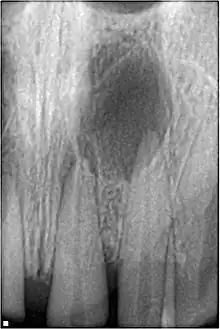

Pulpal necrosis

Pulp necrosis usually occurs either as ischaemic necrosis (infarction) caused by disruption to the blood supply at the apical foramen or as an infection-related liquefactive necrosis following dental trauma (2). Signs of pulpal necrosis include[42]

- Persistent grey colour to tooth that does not fade

- Radiographic signs of periapical inflammation

- Clinical signs of infection: tenderness, sinus, suppuration, swelling

Treatment options will be extraction for the primary tooth. For the permanent tooth, endodontic treatment can be considered.

Pulpal obliteration

4–24% of traumatized teeth will have some degrees of pulpal obliteration that is characterized by the loss of pulpal space radiographically and yellow discolouration of the clinical crown. No treatment is needed if it is asymptomatic. Treatment options will be extraction for symptomatic primary tooth. For symptomatic permanent tooth, root canal treatment is often challenging because the pulp chamber is filled with calcified material and the drop-off sensation of entering a pulp chamber will not occur.[44]